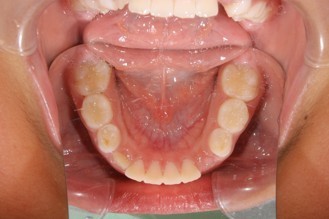

1期矯正治療の症例写真

1期矯正治療終了後の症例写真

第2大臼歯萌出完了

• 主訴:前から2番目の歯が後ろ側に生えている

• 診断あるいは主な症状:叢生

• 年齢:10歳(治療開始年齢)

• 治療に用いた主な装置:マルチブラケットによる歯列矯正(小児矯正)

• 抜歯部位:なし

• 治療期間:1年3ヶ月

• 治療回数:17回(矯正治療を目的とした来院)

• 治療費概算:508,000円(税込)